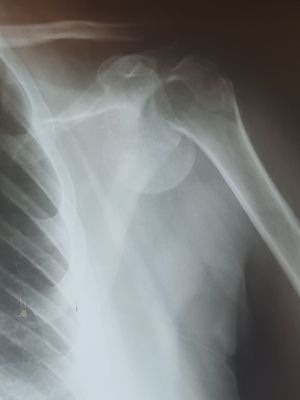

proximal humerus fracture

Orthopedicsurgery

Traumasurgery

Traumatology